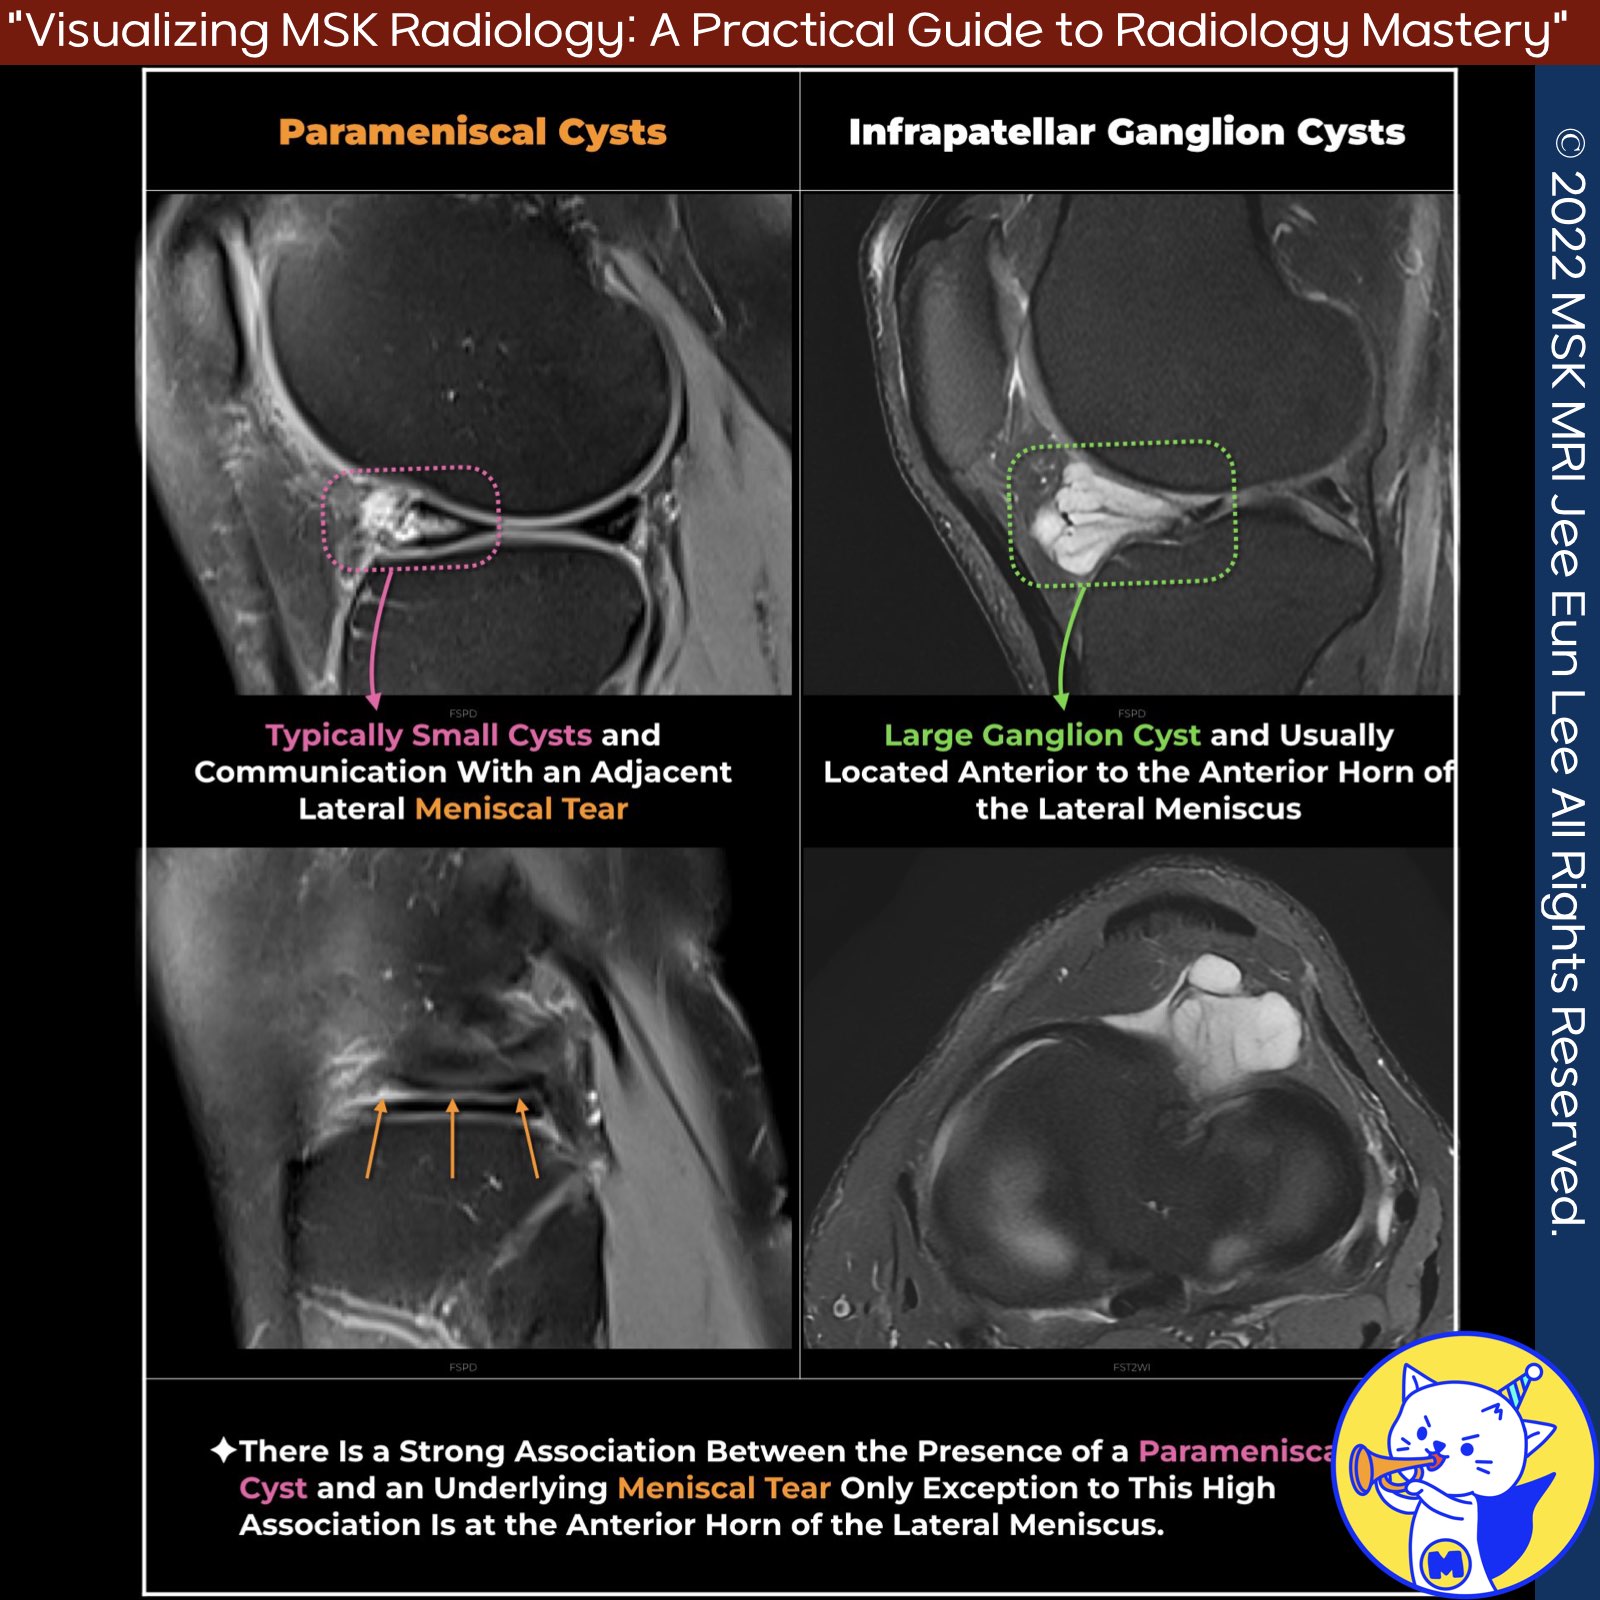

📌 Hoffa’s Fat Pad Ganglion Cysts and Parameniscal Cysts

✅ Hoffa’s Fat Pad Ganglion Cysts

- Hoffa’s fat pad ganglion cysts are most commonly found in the Hoffa fat pad, typically adjacent to the anterior horn of the lateral meniscus .

- On MR imaging, ganglia appear as well-defined, uni- or multi-loculated, fluid-like T2 hyperintense lesions.

- Depending on their protein content, ganglia may be hypo- or isointense on T1-weighted sequences .

- An uncomplicated ganglion appears as a well-defined homogeneous non-enhancing fluid-filled collection on MRI.

✅ Parameniscal Cysts

- On T2-weighted imaging, a parameniscal cyst is a high-signal-intensity fluid collection either directly overlying a meniscus or adjacent to a meniscus with a fluid track connecting to the periphery of a meniscus.

- There is a strong association between the presence of a parameniscal cyst and an underlying meniscal tear.

- The reported association between parameniscal cysts and meniscal tears has ranged from 90% to 100% in MRI series, except at the anterior horn of the lateral meniscus, where an underlying meniscal tear was found in only 64% of patients with these parameniscal cysts.

✅ Differences Between Ganglion Cysts and Parameniscal Cysts

- A parameniscal cyst can simulate a ganglion but is typically smaller and associated with an underlying meniscal tear.

- Confirming a parameniscal cyst is based on depicting a communication with an adjacent meniscal tear on any pulse sequence.

- Synovial fluid extrusion secondary to complex and horizontal meniscal tears (lateral more than medial) results in meniscal cyst formation, which may project into Hoffa’s fat pad.